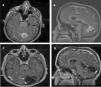

Los hemangiopericitomas intracraneanos (HPC) son tumores de muy baja frecuencia, alta recidiva local y riesgo de metástasis extracraneal. El objetivo del siguiente trabajo es presentar los resultados en el tratamiento de los HPC en nuestra institución en los últimos 20años y realizar una revisión de la literatura del tema.

ResultadosUn total de 19 pacientes cumplieron los criterios de inclusión. La mediana de seguimiento fue de 96meses (12-230). La mortalidad fue del 21% (n=4). El 57,9% presentaron al menos una recidiva tumoral (n=11) (con una recurrencia del 6, del 67 y del 90% a 1, 5 y 10años, respectivamente). Cinco pacientes presentaron metástasis extracraneal. Tuvieron mayor sobrevida los pacientes con tumores <6cm (p<0,05).

ResultsA total of 19 patients fulfilled inclusion criteria. The median follow up was 96 months (12-230). The mortality rate was 21% (n=4). 57.9% of patients presented at least one tumor recurrence (n=11) (recurrences of 6%, 67% y 90% at 1, 5 and 10years). Five patients presented extracranial metastasis. Patients with tumors <6cm had greater survival (P<.05).